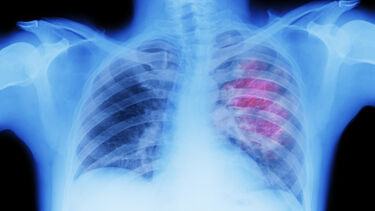

POLARIS (Pulmonary, Lung and Respiratory Imaging Sheffield)

Developing MRI technology and expediting into clinical research and practice.